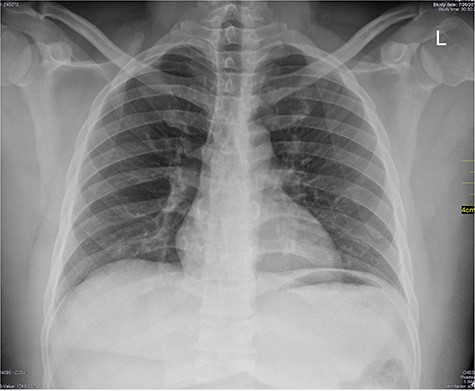

Chest X-ray was normal as shown in Fig. 1. Focused abdominal sonography for trauma (FAST) scan showed mild left perihepatic collection necessitating a thoracoabdominal computerized tomography (CT)-scan which showed external oblique muscle laceration with intermuscular air lucencies and grade 2 hepatic injury as shown in Figs 2–4. Other blood work-up were normal. No other injury was found on secondary survey. His wound was explored under local anaesthesia, primarily repaired, and he was discharged after 24 h of close observation.